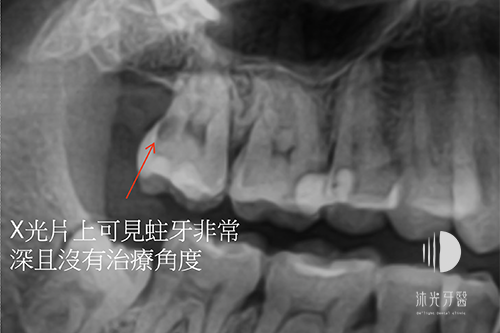

治療前